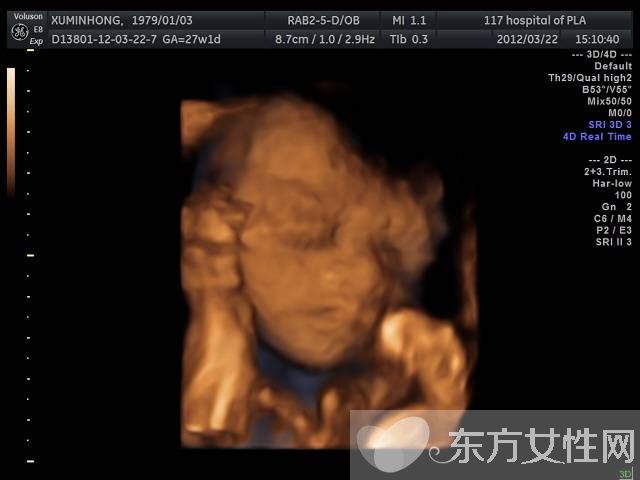

普通B超和彩色B超都是二维平面图像,这两种技术仍在使用,但由于观测效果较为依赖羊水量和胎儿体位,一旦在怀孕晚期羊水减少或者胎儿面向母亲的背部,观测效果就不太理想。而且,二维图像不能满足准妈妈们“看到”宝宝模样的愿望。因此,最近几年,随着计算机技术的发展,又出现了三维B超,也就是将二维图像合成模型,透过屏幕可从各个方位观察胎宝宝。

三维彩超、四维彩超的图像是后期生成的,并不是说观察到的图像就是三维、四维的,而是仍然用普通彩超观察,然后通过仪器中的转换软件将观察到的平面图像转成三维、四维的立体图像,使不懂B超图像的人也能看出胎儿的模样。而三维和四维的区别就在于在一个“时间维”,也就是说,前者是图片,后者是录像,可以让孕妈妈看到胎儿一连串的动作。